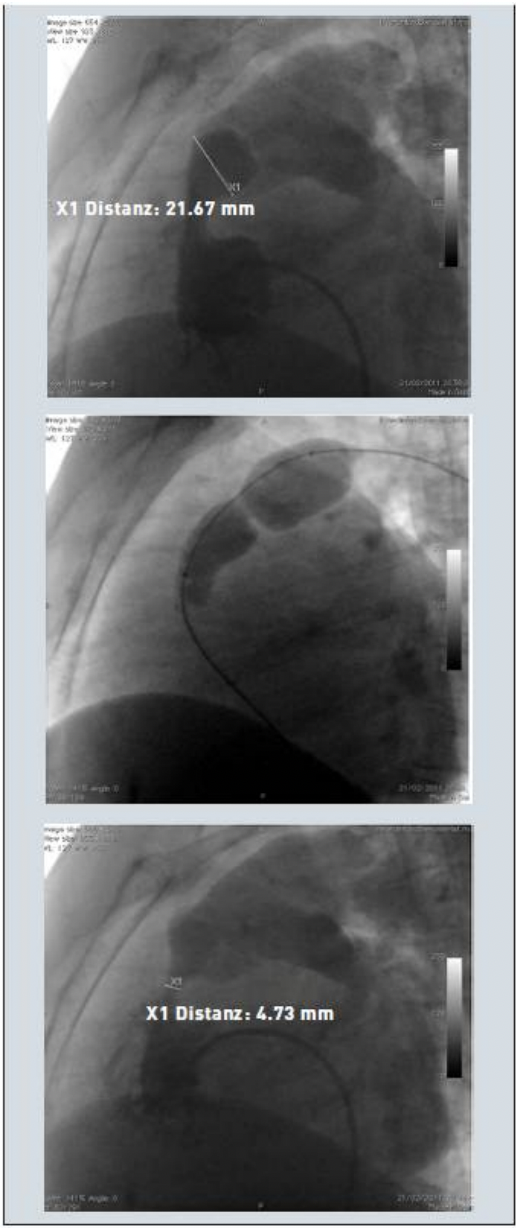

Hình 1. Các bước nong van động mạch phổi